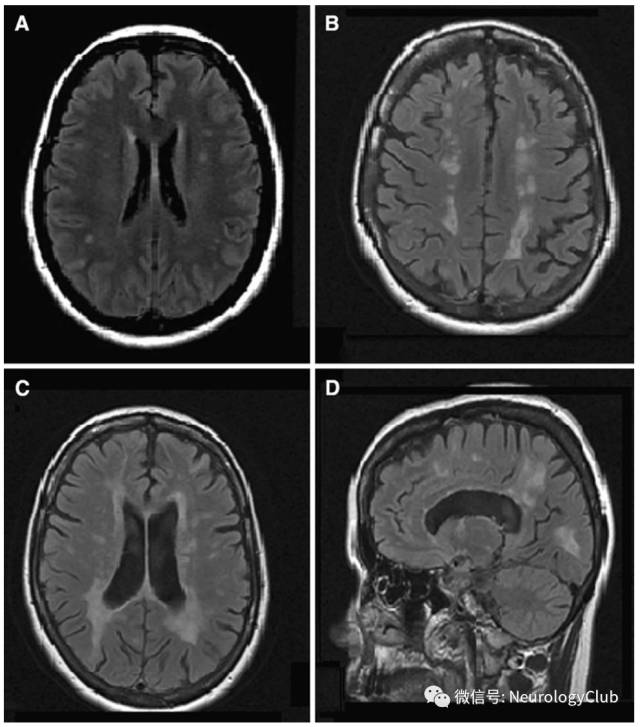

(图16:A-B:典型实质病变,从间脑延伸至基底节;C:多发性硬化样病灶;D:非特异性白质病变)

(图18:FLAIR可见皮质下白质受累,貌似脱髓鞘病变)

(图19:可见弥漫对称白质病变伴脑干受累)